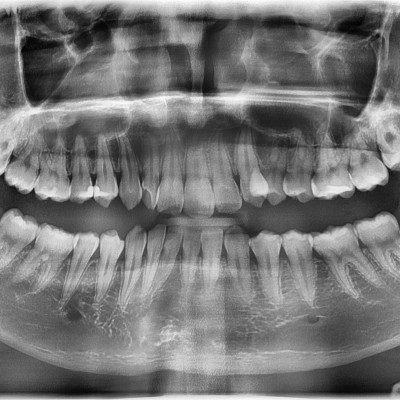

#38, 48 사랑니 발치 #38, 48 사랑니 발치 구강 외과 전문의가 당일 발치했습니다. -------------------------..

작성자 이턱이 작성일 02-04 조회 1